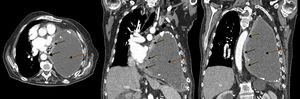

Ante la escasa mejoría clínica tras la evacuación de líquido pleural junto con los datos sugestivos de insuficiencia cardíaca derecha se realizó ecocardiografía transtorácica, objetivando una masa hipoecogénica en la pared inferolateral del ventrículo izquierdo, con dilatación de la aurícula izquierda, ligero derrame pericárdico, FEVI conservada y vena cava inferior dilatada sin colapso inspiratorio. Se realizó TC toracoabdominal, apreciándose una masa de partes blandas en la pared medial y caudal del hemitórax izquierdo, de 6×3cm, con infiltración pericárdica, efecto masa y pequeño derrame pericárdico asociado. Comparativamente con estudios previos se evidenció un importante incremento de la colección pleural conocida, que se encontraba ocupando la práctica totalidad del hemitórax, produciendo atelectasia compresiva del pulmón con desviación mediastínica contralateral y compresión cardíaca (fig. 1).

TC de tórax con contraste, corte axial (izquierda) y coronales (centro y derecha:): masa pleural en pared medial y caudal de hemitórax izquierdo con infiltración pericárdica (flechas continuas) y gran colección en hemitórax izquierdo correspondiente con piotórax crónico (flechas discontinuas), produciendo en su conjunto desplazamiento mediastínico contralateral y compresión cardíaca.